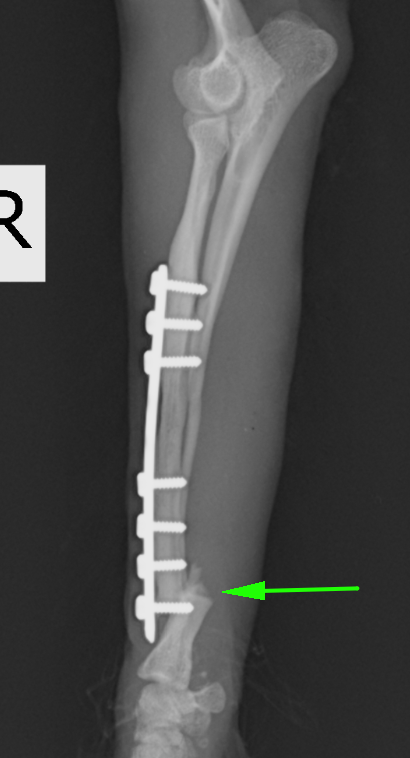

次の症例は以前の骨折を他院にてプレート固定していたそうですが、ある時からまた足を上げるとのことで来院しました。矢印の部分で折れてしまっています。

入っていたプレートを抜去したところです。入っていたところの遠位(左写真の左側)に骨折線があります。プレートのスクリューホールに骨が入り込むのでボコボコとした形になります。

今回の手術後の写真です。非常に長いプレートが入っているのは、手術して再骨折があった場合にはもとのプレートよりも長いプレートを入れる必要があるからです。また、骨が痩せて細くなっているケースが多いので術後も注意が必要です。

術後レントゲンです。橈骨全域に渡ってプレートが入っています。近位は少し外側に曲がっているため、最初からプレートを曲げています。術後2日目には患肢を使っての歩行が可能でした。また、キャスト(ギプス)も使わないので、ストレスなく生活が可能です。術後1ヶ月半ほどで正面のプレートを抜去しています。